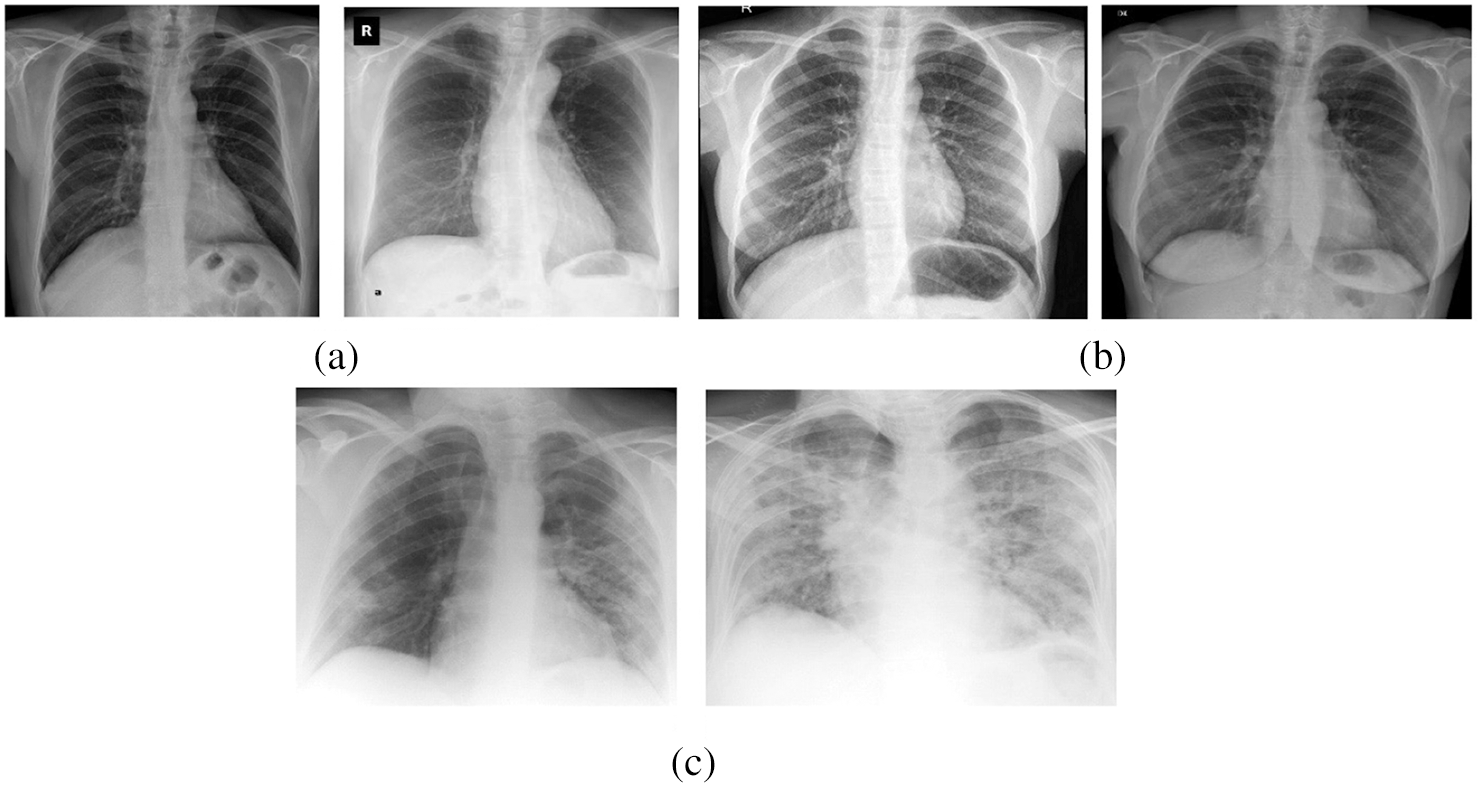

The performance of the proposed OHFE-ODNN method was tested utilizing a set of chest X-ray [32] image dataset including 220 images from COVID-19 positive patients, 27 Normal patients and 11 images from SARS-11 positive patients. Some of the test images are displayed in Fig. 4. The parameters contained in the simulation procedure are learning rate: 0.0001, momentum: 0.9, batch size: 128 and epoch count: 140.

Figure 4: (a) Covid-19 (b) normal (c) SARS